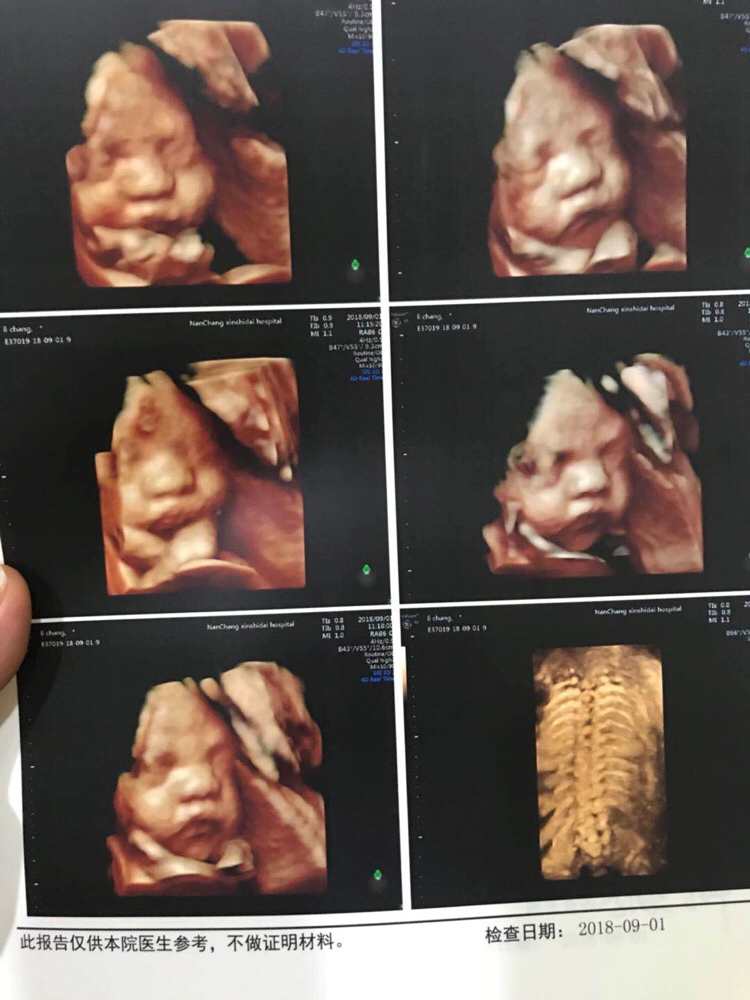

孕30周+3天

诚心跪求下次产检四维项目,一次过,保佑🙏